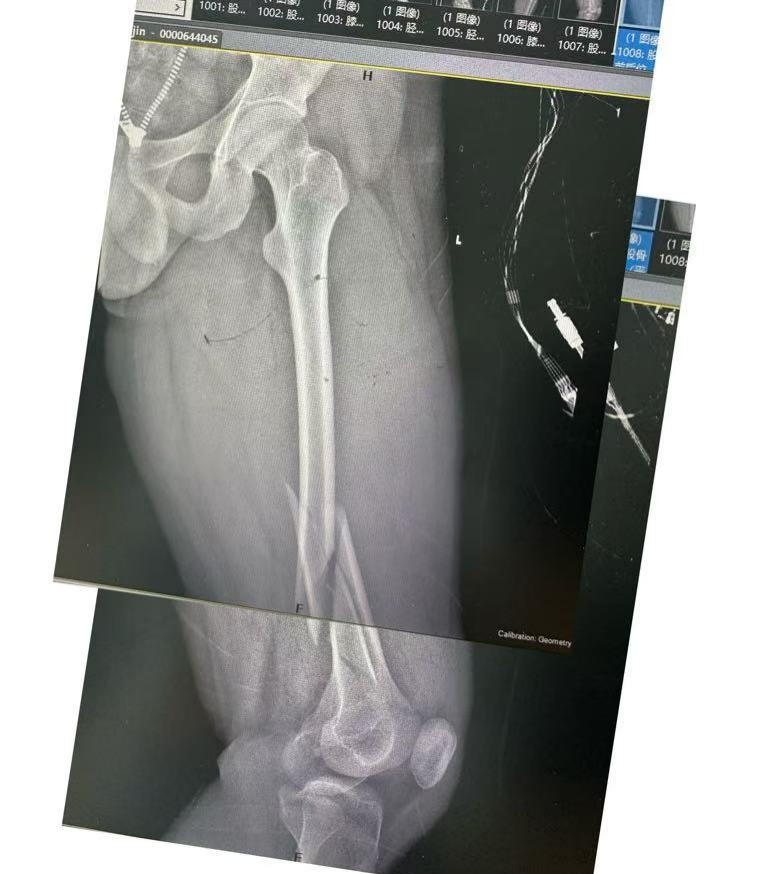

患者面色苍白,伤肢肿胀呈进行性加重,足背动脉搏动微弱,几不可及。值班医生迅速接诊,细致开展体格检查,凭借扎实的专业功底和高度责任心,第一时间判断为「左股骨下段粉碎性骨折,下肢血管及肢体动静脉损伤」。他深知,若救治延迟,不仅肢体可能坏死丧失,更将直接威胁患者生命。

无影灯下,硬仗打响。麻醉成功后,由创伤中心组成的手术团队立即投入战斗。术中证实股动静脉完全损伤、左股骨下段粉碎性骨折。在积极抗休克的同时,团队精细吻合修复血管,成功恢复下肢血供;随即为骨折部位清创复位、外固定架临时固定,最大限度控制损伤、稳定生命体征。术后患者转入 ICU,进入下一阶段严密监护与综合治疗。

术后,ICU 团队 24 小时值守,密切监测循环、呼吸及肢体血运,精准调控抗凝、抗休克抗及营养支持方案,为患者平稳度过危险期提供了坚实保障。2 月 24 日,待病情稳定后,患者顺利接受了「左股骨粉碎性骨折闭合复位髓内钉内固定术」。